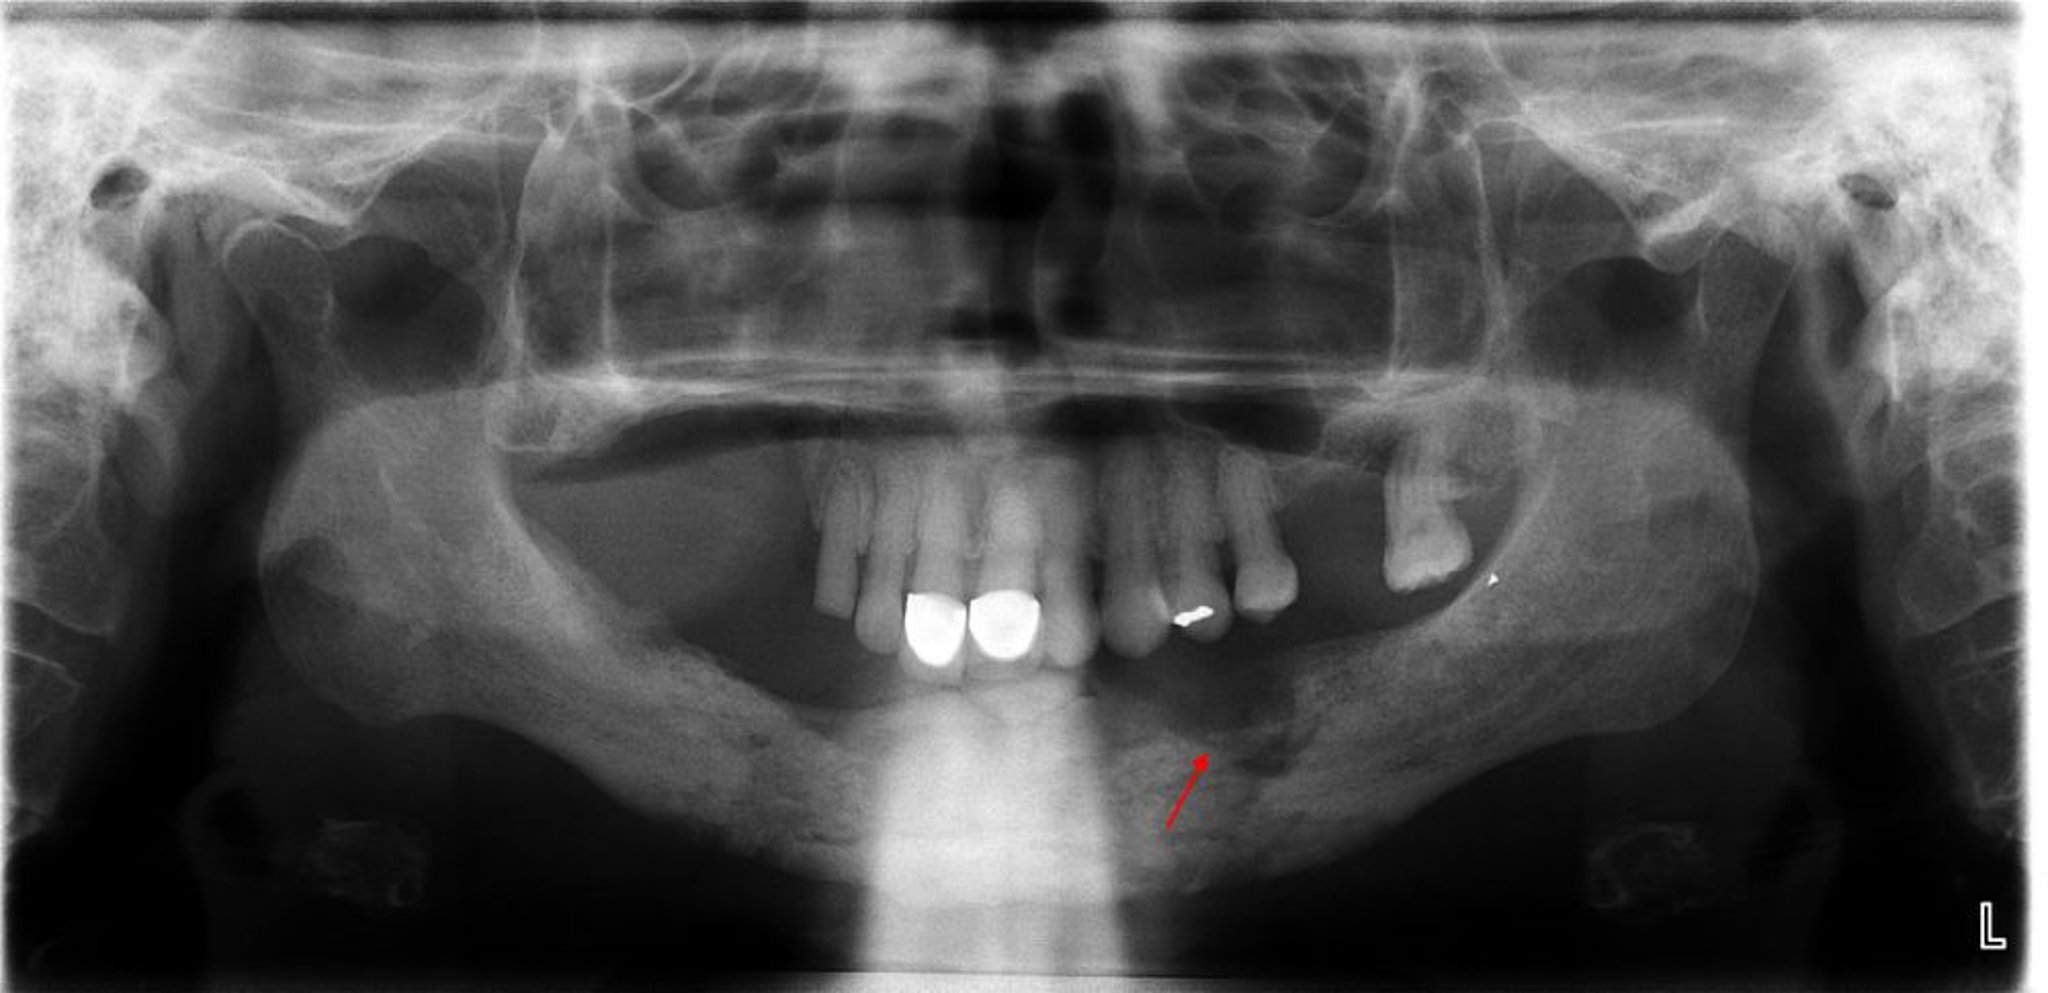

Essa radiografia revela osteomielite com sequestro evidente (osso não viável) observado no quadrante mandibular posterior esquerdo.

Imagem cedida por cortesia de Byron (Pete) Benson, DDS, MS, Texas A&M University Baylor College of Dentistry.